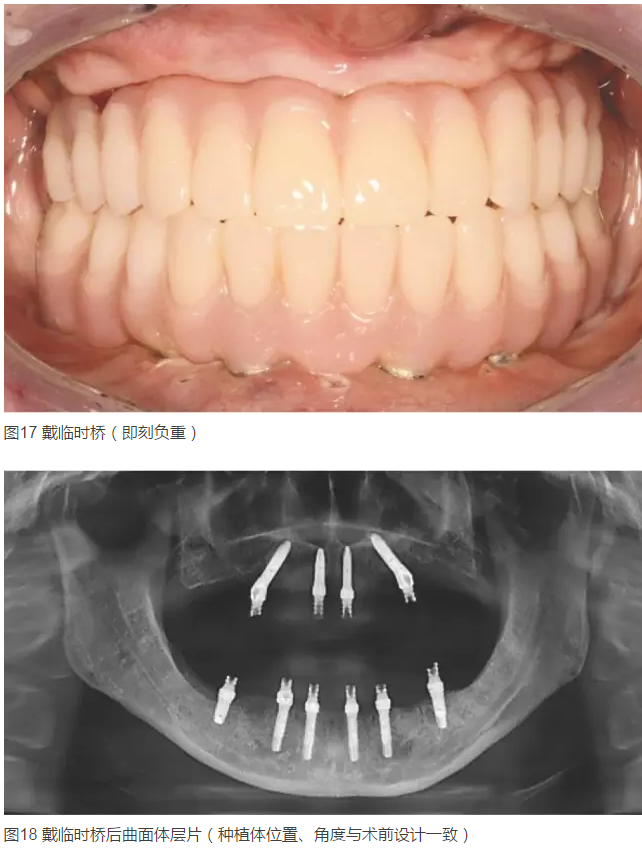

2015年5月25~29日,由中華口腔醫(yī)學(xué)會(huì)民營(yíng)口腔醫(yī)療分會(huì)主辦的第八次中國(guó)民營(yíng)口腔年會(huì)在江蘇省蘇州太湖國(guó)際會(huì)議中心舉辦。會(huì)議期間舉辦的“首屆中國(guó)民營(yíng)口腔種植病例點(diǎn)評(píng)”展評(píng)是中國(guó)民營(yíng)口腔界繼去年正畸病例大賽后第二次舉辦全國(guó)規(guī)模的醫(yī)學(xué)專業(yè)展評(píng),經(jīng)層層篩選后的10位民營(yíng)口腔醫(yī)師進(jìn)入總決賽。  本報(bào)陸續(xù)刊登了本次展評(píng)的4例優(yōu)秀病例、3例季軍病例及2例亞軍病例后,本期繼續(xù)為您刊登來(lái)自廣東省深圳市許慶龍口腔診所金春禮醫(yī)師的冠軍病例“計(jì)算機(jī)技術(shù)在口腔種植方面的應(yīng)用”。

患者女,42歲。1年前因牙周病拔除全口牙齒,行全口活動(dòng)義齒修復(fù),現(xiàn)自覺(jué)影響咀嚼和生活來(lái)診。要求:牙種植修復(fù)后即刻可使用。